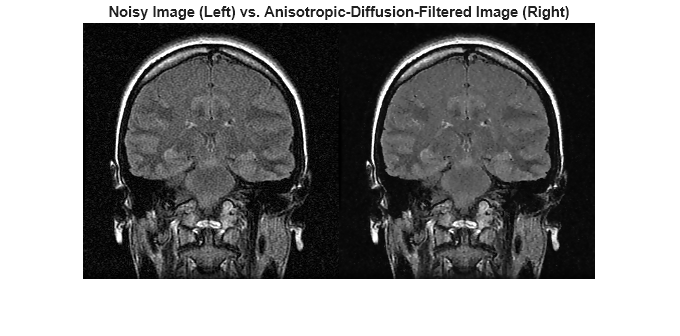

Cargue el volumen de una resonancia magnética 3D en escala de grises con ruido.

load mristackRealizar una reducción del ruido con capacidad para detectar bordes en el volumen mediante difusión anisotrópica. Para evitar suavizar en exceso las características de bajo contraste en el cerebro, disminuya el número de iteraciones respecto al número predeterminado, 5. Como contrapartida, se elimina menos ruido.

diffusedImage = imdiffusefilt(mristack,'NumberOfIterations',3);Para comparar en detalle la imagen con ruido y la imagen filtrada, muestre el décimo corte de ambas.

imshowpair(mristack(:,:,10),diffusedImage(:,:,10),'montage') title('Noisy Image (Left) vs. Anisotropic-Diffusion-Filtered Image (Right)')

Calcule la puntuación del Evaluador de la calidad de imágenes naturales (NIQE) promediada en todos los cortes del volumen. La puntuación del NIQE proporciona una medida cuantitativa de la calidad de la imagen que no requiere una imagen de referencia. Las puntuaciones del NIQE más bajas reflejan una mejor calidad perceptiva de la imagen.

The NIQE score of the noisy volume is 5.7794.

The NIQE score using anisotropic diffusion is 4.1391.

La puntuación del NIQE es coherente con la observación de la reducción del ruido en la imagen filtrada.